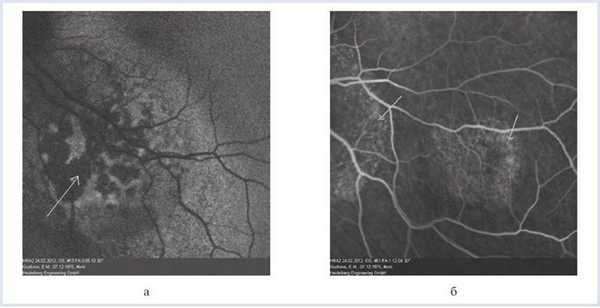

OS — макулярно и парамакулярно в 1,5 PD от диска зрительного нерва по меридианам с 14.30 до 20.30 часов определялся проминирующий желтый слабопигментированный очаг с бугристой поверхностью, нечеткими неровными границами, размером 4×5 PD (рис. 4, а). Рисунок 4. Офтальмоскопия юкстапапиллярного очага (а) и малого фокуса (б). Кнаружи от основного фокуса диагностирован слегка проминирующий очаг желто-коричневого цвета, с нечеткими неровными границами, с бугристой поверхностью (см. рис. 4, б).

Флюоресцентная ангиография:

OS — в ранние фазы исследования определяется зона гипофлюоресценции в центральном отделе очага, в ранние венозные фазы — ангиопатия сосудов сетчатки, в средние венозные фазы — гиперфлюоресценция по периферии фокуса с формированием симптома «россыпи крупы», сохраняющегося до поздних фаз исследования.

В зоне наружного очага — симптом «россыпи крупы», сохраняющийся до поздних фаз исследования (рис. 5). Рисунок 5. Флюоресцентная ангиография метастатической карциномы хориоидеи. Гипофлюоресценция в ранние фазы исследования — белая стрелка (а); «россыпь крупы» (стрелки) юкстапапиллярного очага и малого фокуса (б).

OS — над очагами мелко- и крупнобугристое изменение хориоидального профиля, ретиношизис, мелкие и крупные гиперрефлективные депозиты в слое нейроэпителия, сохранение анатомо-топографической структуры хориокапилляров. На уровне больших сосудов хориоидеи визуализируется низкорефлективная полоса, передняя и задняя границы очага, а также мелкие округлые гиперрефлективные включения во внутренних слоях хориоидеи (рис. 6). Рисунок 6. СОКТ метастатической карциномы хориоидеи юкстапапиллярного очага (а) и малого фокуса (б). Красная стрелка — мелкобугристое изменение хориоидального профиля; зеленая стрелка — интраретинальные депозиты; синяя стрелка — хориоидальный очаг с визуализацией хориокапилляров.

На основании совокупности результатов проведенных исследований диагностирована метастатическая карцинома хориоидеи. Больная направлена к онкологу для проведения повторного курса системной полихимиотерапии.

В первом случае гипофлюоресценция в зоне очага с гиперфлюоресценцией по его периферии в совокупности с томографически выявленной отслойкой РПЭ и сохранением ровного профиля мембраны Бруха позволяют снять диагноз вторичной злокачественной опухоли хориоидеи и установить возрастную макулярную дегенерацию.

Во втором случае гипофлюоресценция в ранние фазы исследования, симптом «россыпи крупы» в совокупности с томографически определяемым мелкобугристым изменением хориоидального профиля, наличием депозитов в слоях сетчатки, ретиношизисом дают возможность установить диагноз метастатической карциномы хориоидеи.